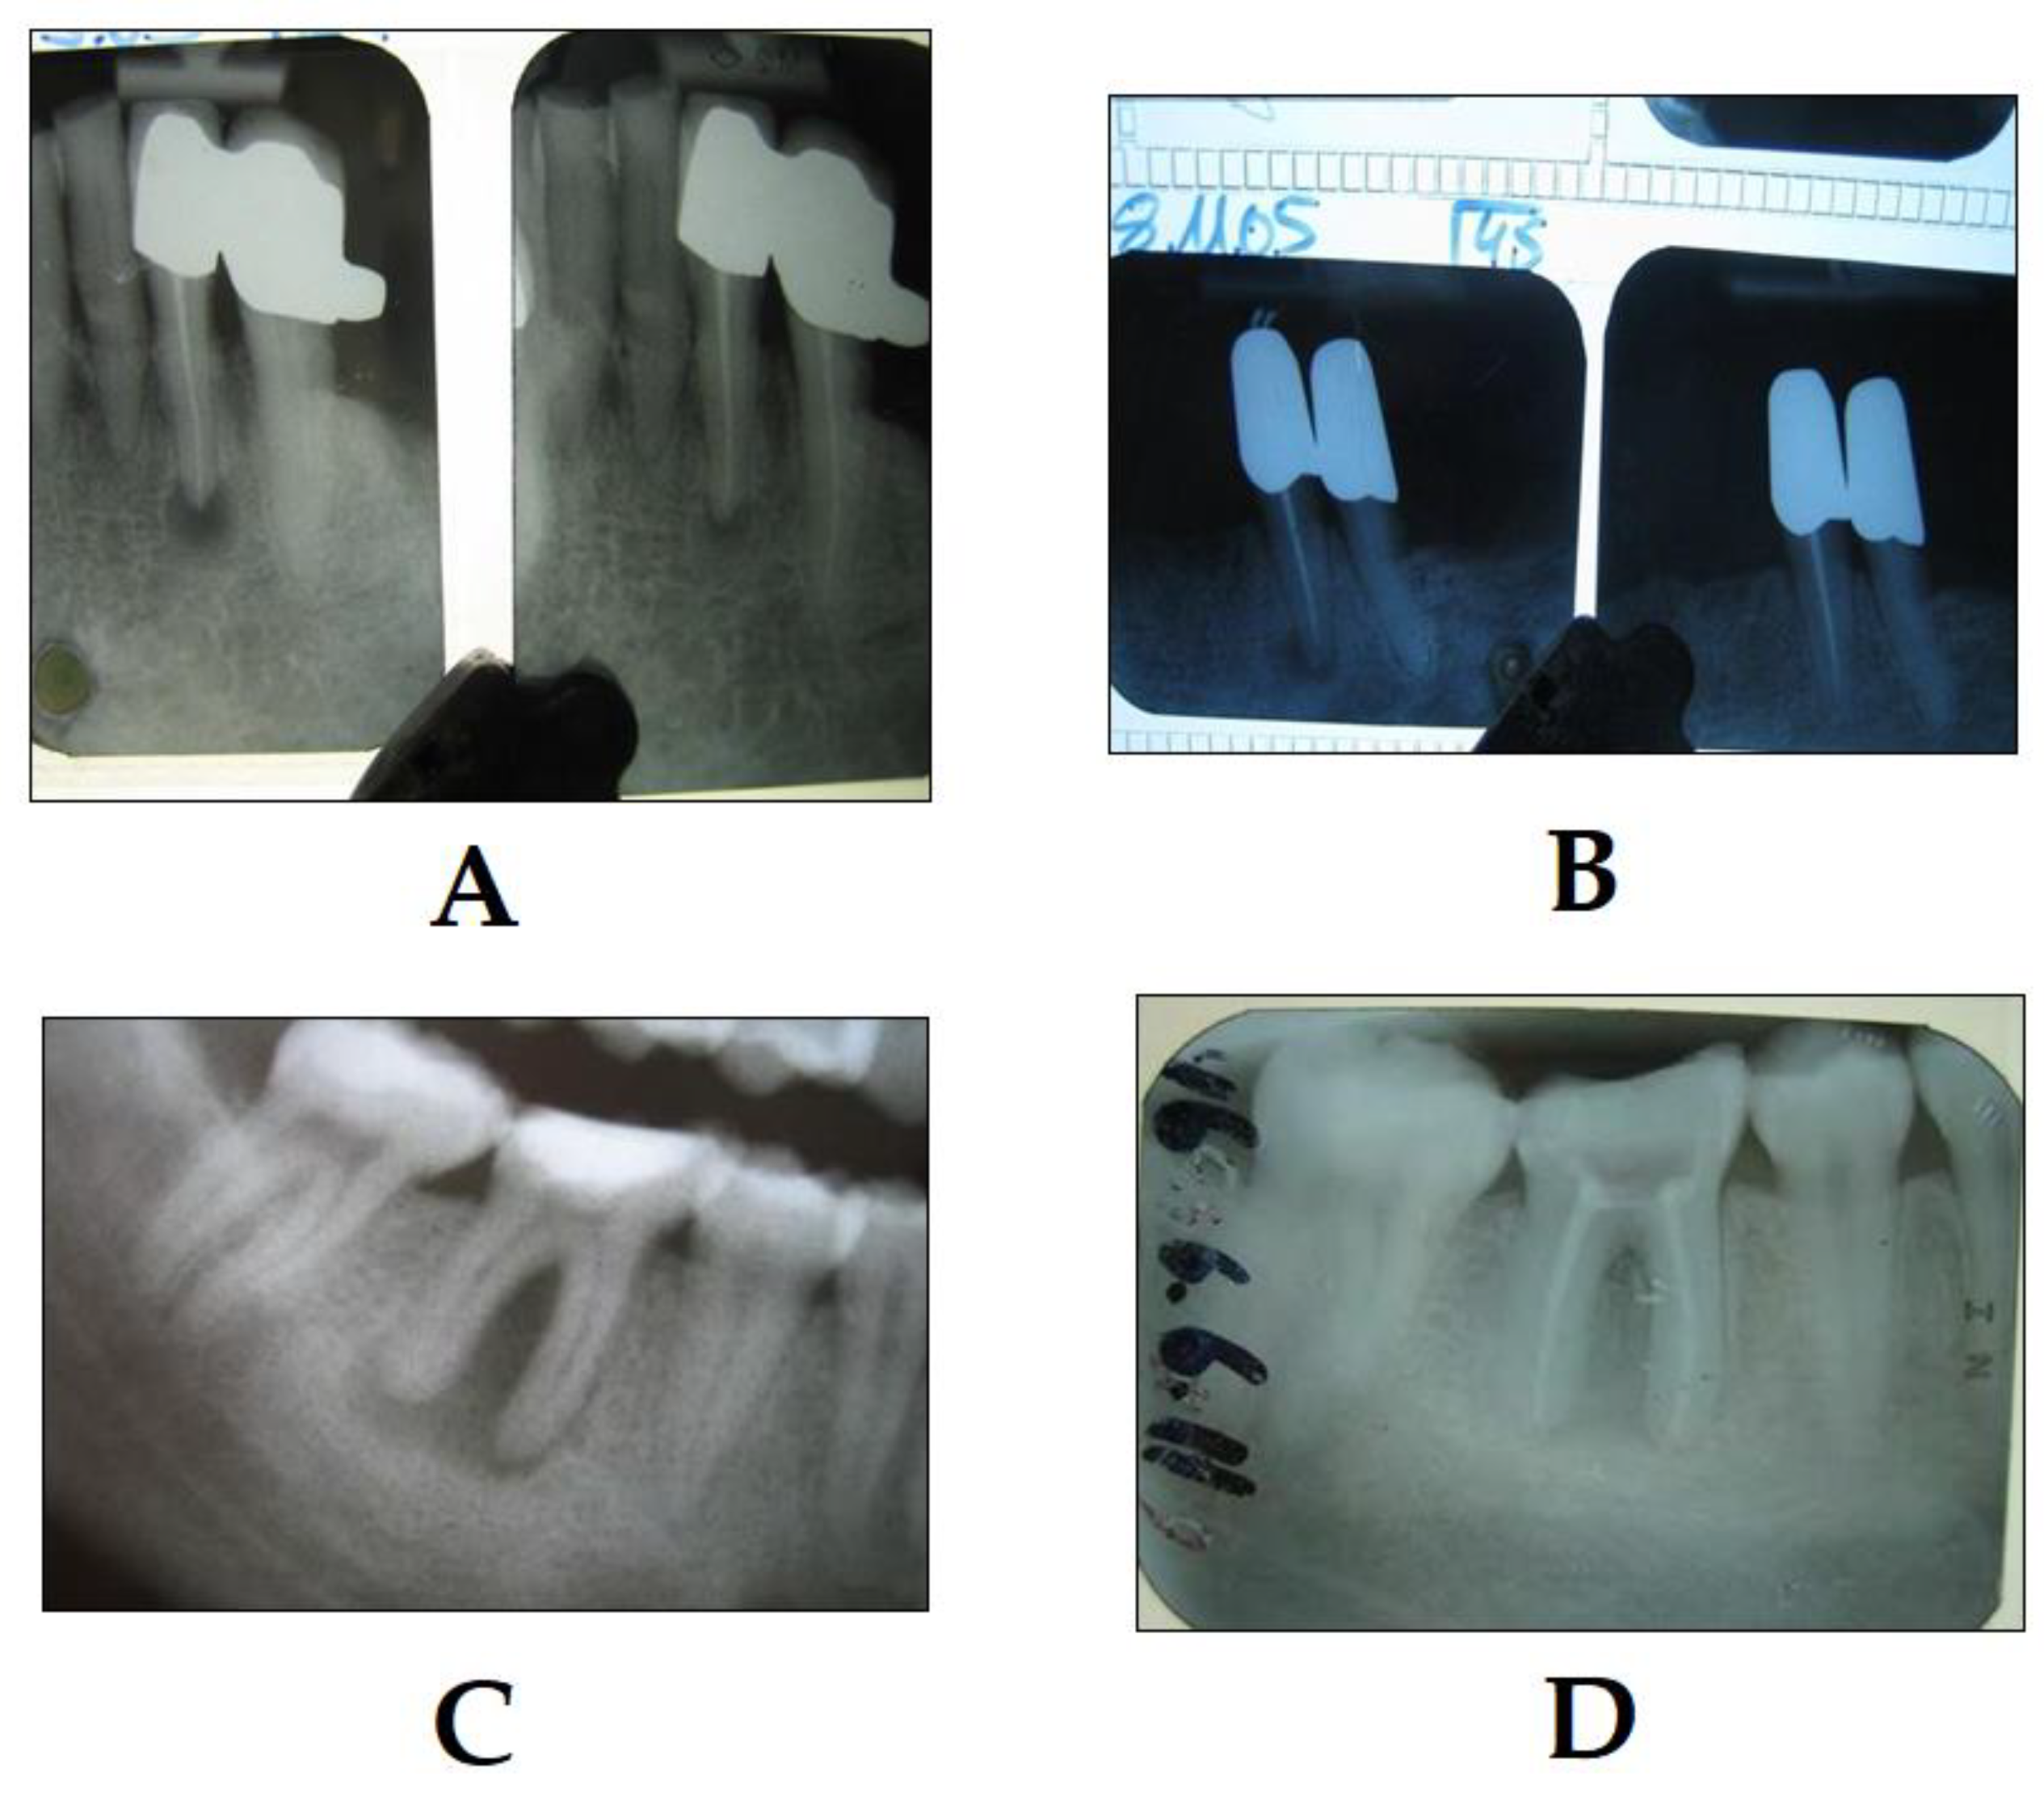

3.2. PDT in Endodontics

- Trindade, A.C.; De Figueiredo, J.A.P.; Steier, L.; Weber, J.B.B. Photodynamic therapy in endodontics: A literature review. Photomed. Laser Surg. 2015, 33, 175–182. [Google Scholar] [CrossRef]

- Garcez, A.S.; Nuñez, S.C.; Hamblin, M.R.; Ribeiro, M.S. Antimicrobial effects of photodynamic therapy on patients with necrotic pulps and periapical lesion. J. Endod. 2008, 34, 138–142. [Google Scholar] [CrossRef]